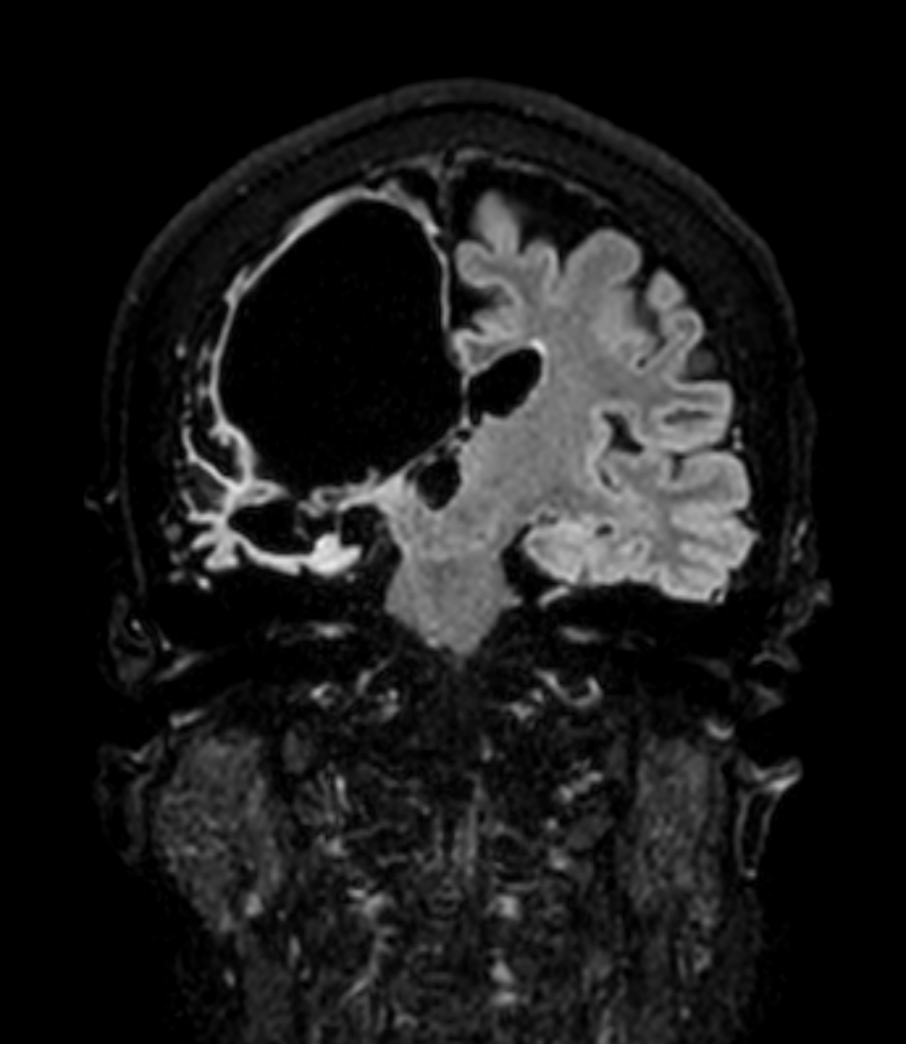

Coronal 3D BrainVIEW FLAIR (without Compressed SENSE)

Coronal 3D BrainVIEW FLAIR (Compressed SENSE)